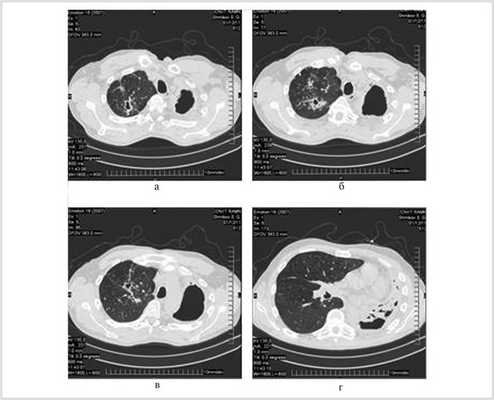

При компьютерной томограмме выявлены цирротические изменения левого легкого с обширной полостью эмпиемы и множественными мелкими полостями в коллабированном легком. Правое легкое уменьшено в объеме за счет фиброзных изменений верхней доли, в которой определялись три каверны диаметром до 2 см, имелось очаговое обсеменение нижних долей (рис. 1).

Рис. 1. Компьютерные томограммы больного Ш. до операции.

В мокроте выявлены МБТ (+++), устойчивые к стрептомицину, изониазиду, рифампицину, канамицину и пиразинамиду.

После 2 мес интенсивной терапии 11.04.11 выполнена операция: трансстернальная трансмедиастинальная окклюзия левого главного бронха с одномоментной верхней лобэктомией справа.